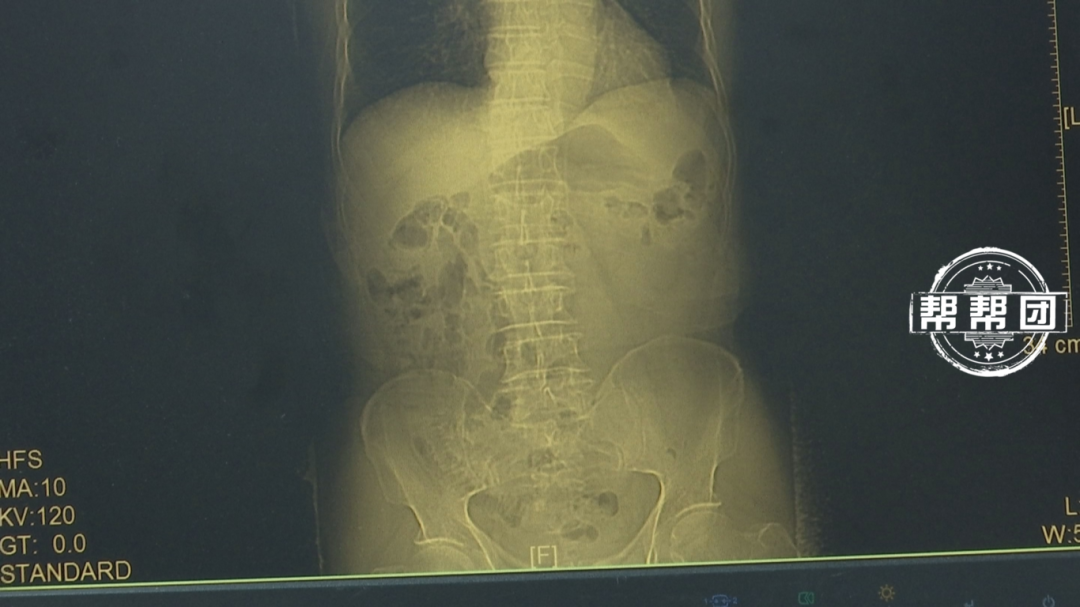

此前也有类似病例。34岁宝妈张女士(化名)去医院体检时发现,干干净净的胃里竟有一小片糜烂,活检病理显示为恶性程度极高的印戒细胞癌。经与医生沟通发现,这可能与她三餐不规律、经常吃腌制食品有关。